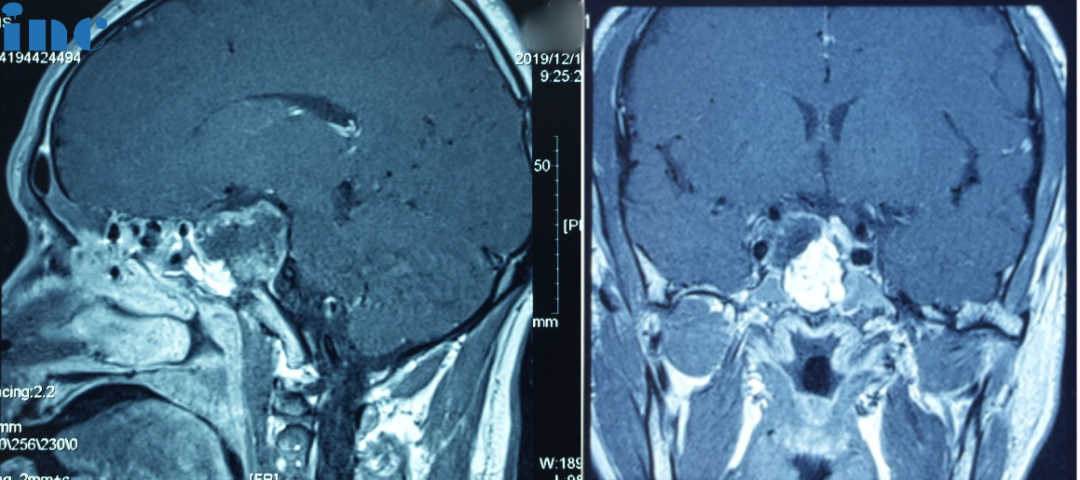

术前:肿瘤体大,广泛累及颅底结构,侵蚀斜坡、鞍内鞍上、海绵窦区,包裹右侧颈内动脉。肿瘤向上推挤视神经、视交叉,到达三脑室底部;向后上方推挤脑干和基底动脉,部分肿瘤边缘与脑干分界欠清。

2019年10月出现无明显诱因的视野缺损,伴视力下降,遂就诊当地医院。行颅脑磁共振检查,提示占位性病变,脊索瘤可能性大。

同年12月行全麻下经鼻年内镜肿瘤切除术,手术顺利。术后病理提示脊索瘤。术后恢复理想,视力视野恢复良好。后因疫情原因,未做术后复查。

2021年,患者再次出现视力下降伴视野缺损。于当地医院行颅脑磁共振检查,提示鞍区脊索瘤复发。

2021年7月7日在全麻下行开颅鞍区肿瘤切除术,术后病理为脊索瘤复发。术后恢复的比一手术会稍微慢一点,但视力视野还是恢复正常。